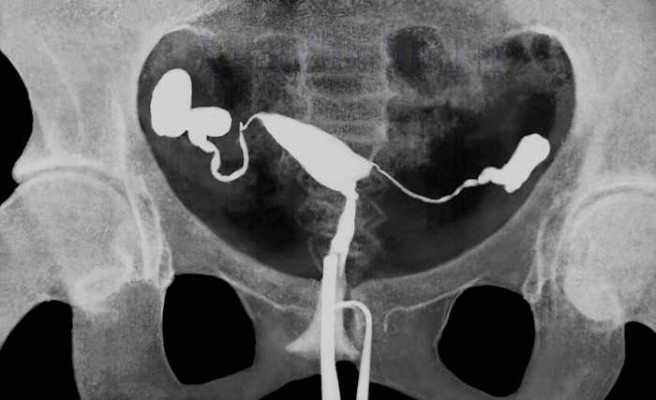

В клинику №1 ВиТерра Беляево к врачу-гинекологу обратилась пациентка С., 26 лет, с жалобами на боли внизу живота и отсутствие беременности. Врачом-гинекологом была назначена гистеросальпингография.

Под наблюдением врача-гинеколога и врача-рентгенолога ВиТерра пациентке в полость матки было введено йодсодержащее контрастное вещество (Омнипак) и произведены рентгенологические снимки.

Полость тела матки нормально сформирована и беспрепятственно заполняется контрастным веществом. Тень полости тела матки правильной треугольной формы, с чёткими и ровными контурами, дефектов контрастирования не наблюдается. Правая маточная труба контрастирована на всём протяжении, расширена в истмическом отделе до 2 мм и ампулярном отделе до 8 мм. Левая маточная труба контрастирована на всём протяжении, расширена в ампулярном отделе до 5 мм. В брюшную полость контраст не поступает.

Заключение врача-рентгенолога: Рентгенологические данные за сактосальпинкс с обеих сторон. Маточные трубы непроходимы.